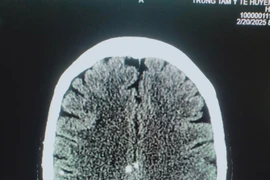

Đột ngột xuất hiện tình trạng méo miệng, nói khó, người đàn ông đi khám được chẩn đoán nhồi máu não giờ thứ 2 và cấp cứu kịp thời trong khoảng thời gian vàng. Đáng chú ý, bệnh nhân đang điều trị tình trạng tăng huyết áp nhiều năm nay.

Cấp cứu đột quỵ trong thời gian vàng giúp nâng cao cơ hội sống sót cho người bệnh, bởi chỉ cần chậm 1 phút, người bệnh có thể sẽ mất đi gần 2 triệu tế bào não. Can thiệp, điều trị đột quỵ tốt nhất cần trong khung giờ này.